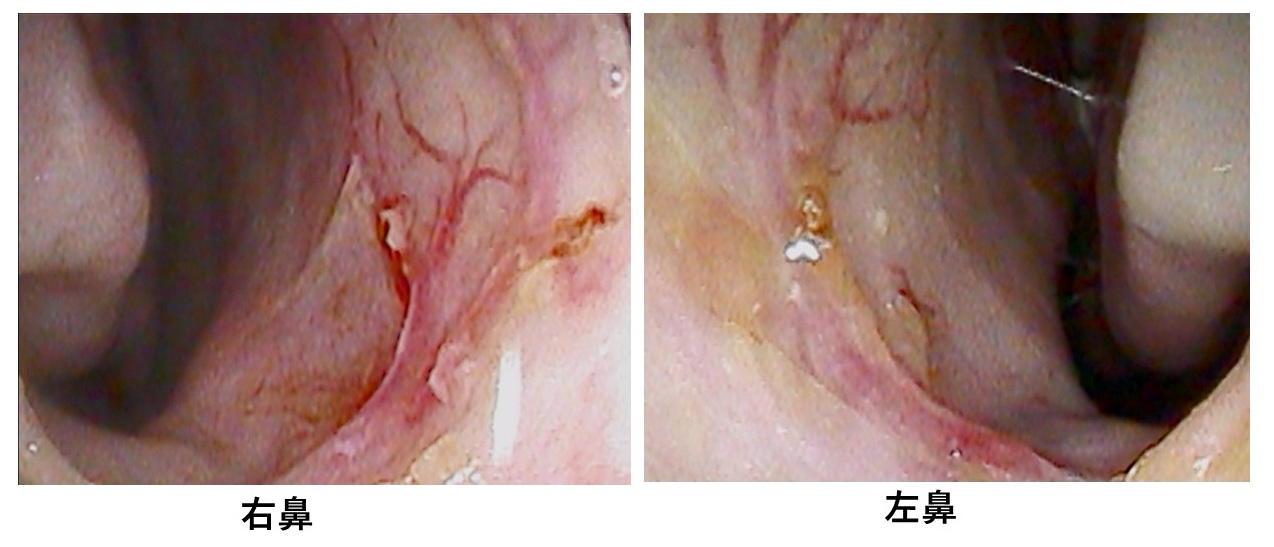

鼻👃の中を診てみます↓

出血点がありました。

どこかと言いますと↓

赤丸部分です。

キーゼルバッハ部位で、血管が露出して破綻しやすくなっています。

「キーゼルバッハ部位」とは、鼻の入り口付近から1〜2㎝にあり、毛細血管が集中し粘膜も薄いため、出血しやすい場所です。